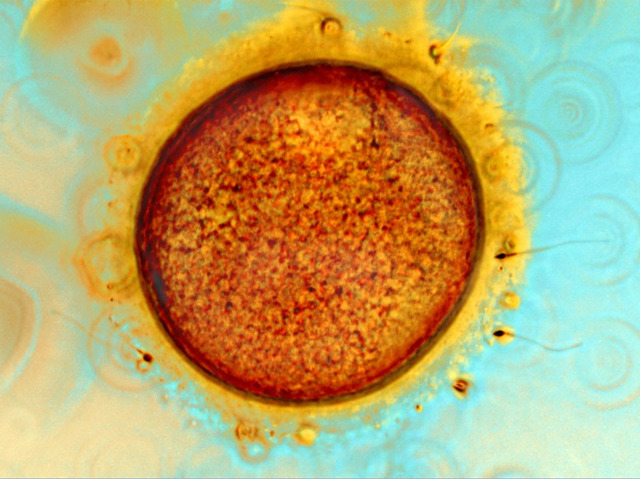

Sir Robert Edwards, who was born on this day in 1925, won the Nobel Prize in Physiology or Medicine for the development of in vitro fertilisation (IVF). IVF is the process of fertilising an egg (or ovum) with a sperm in a laboratory dish, and gives women with fertility problems the chance to bear children. Here, the photographer has captured the moment of conception during IVF. For successful fertilisation, the sperm must penetrate the protective cumulus cells surrounding the egg (coloured yellow) and the outer membrane, called the zona pellucida (stained red-brown). Edwards had to overcome significant political and religious resistance to his novel procedure. Nonetheless, in 1978 Louise Brown, the world’s first so-called ‘test tube baby’, was born (though her conception actually took place in a Petri dish). By the time of Edwards’ death in 2013, more than four million births had resulted from IVF.